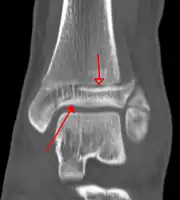

A triplane fracture of the ankle as seen on plain X-ray -